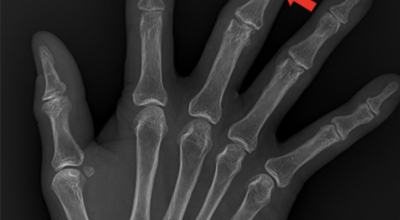

손가락 관절염

관절염은 관절 연골이 훼손되고 관절에 염증성 변화가 일어나는 질환을 의미한다고 하며 관절은 두 개 및 그 이상의 뼈들이 맞닿는 곳을 말한다고 해요. 관절을 이루는 뼈들의 끝은 연골이라는 부드러운 재질로 싸여 있고, 연골은 쿠션처럼 관절이 쉽게 움직이도록 도와 준다고 합니다. 그리고 활막이라고 부르는 섬유질 막으로 싸여 있으며 마찰을 예방하는 활액을 분비해 줍니다.

손가락 관절염 원인

손가락 관절염 치료법은 원인에 따라 달라지며 원인은 크게 양쪽 모두를 의심할 수 있어요. 1개는 관절을 무리하게 활용하던가 노화로 인해 나타나는 퇴행성 관절염이며 다른 1개는 자가면역체계 이상으로 기인해서 나타나는 류마티스 관절염입니다.

퇴행성은 오랜 활용과 반복되는 부담으로 인하여 연골이 닳고 뼈가 변형되는 성격이 있다고 하며, 서서히 발생하며 통증이 일어나게 됩니다. 그리고 손가락의 부종이 어느 관절에 나타났느냐에 따라 의심되는 질병이 다르게 분류 되며 헤버딘 결절이라고 하여 손가락의 첫번째의 관절을 중점으로 혹 형태의 붓기와 변형의 증상이 나타나게 되며 심해질 경우, 일상생활에 지장을 초래할 수도 있겠습니다.